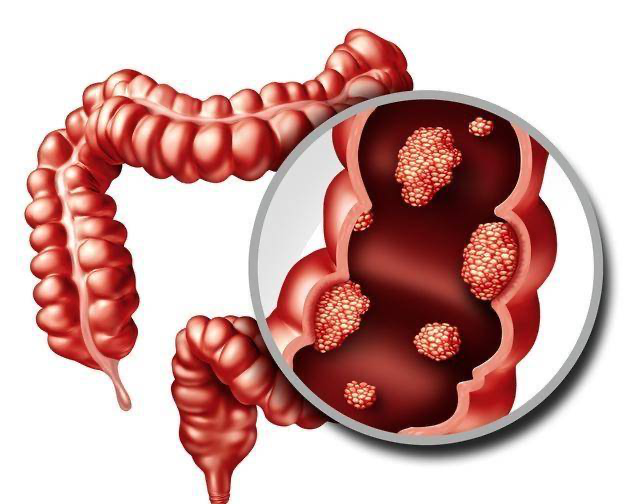

在Juliao等待九个月终于进行肠镜检查后,她终于发现了为什么她在喂养她的小女儿时会有内出血症状的原因:她的结肠里长了肿瘤。

她才三十多岁,但是已经患上了结直肠癌初期。“我真的很欣慰医生们很快就发现了病症,但是我很快就意识到了事情的严重性。”Juliao 需要进行手术切除大约 30 厘米长的下结肠,作为刚刚进行过生产的人,她不得不休假半年多才能康复,现在她正在学习适应消化系统的改变带来生活上的变化。

即便是医疗团队能够治愈癌症,就像他们通常能够做到的那样。外科手术治疗将会极大地改变某人的生活,因为移除肿瘤将意味着切除部分结肠并影响肠功能,在某些情况下还会影响生育功能和性功能。

专家说,诊断出癌症晚期将是一场迫在眉睫的灾难。由于疫情期间筛查和诊断测试的延迟,癌症专家正准备迎接一波患有更晚期疾病的患者。但即使是作为癌症初期患者,结直肠癌也改变了她的生活。 手术后恢复的第一年充满挑战,因为失去了一部分结肠导致她的消化系统工作方式发生重大变化。

Juliao 开始感到疼痛和腹胀,并意识到她的身体根本无法再处理某些食物,从大蒜到某些类型的豆类。“我不得不更频繁地去洗手间,”她补充道。 “这不是我们在社会上真正谈论的事情,但在手术后最初的那段康复时期,我不得不每天大便 10 到 12 次。这不是你可以通过工作和生孩子来解决的事情。我真的哪儿也去不了。”